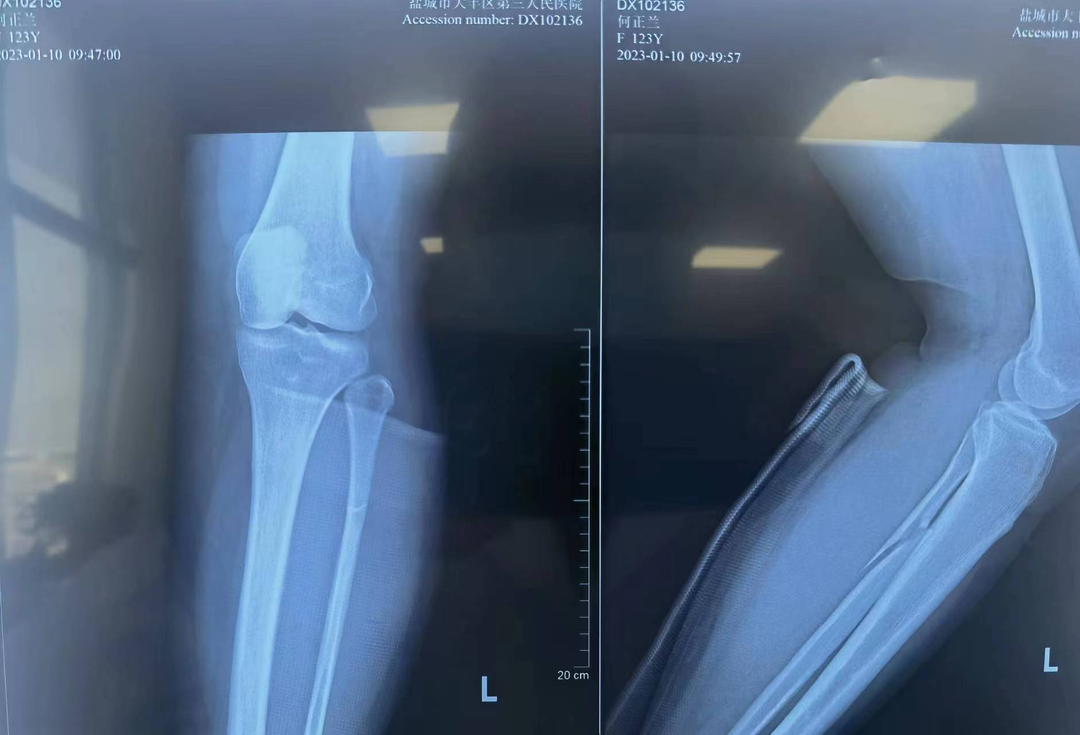

近日,我院急诊收治一名踝关节扭伤病人,患者女性,47岁,就诊时踝关节肿胀较严重,疼痛剧烈,活动受限,查体因疼痛不能完成。 急诊踝关节摄片提示:左踝关节脱位。当晚值班医师立即汇报骨科梁永新主任,根据患者扭伤机制,梁主任指示该患者为一种特殊类型的踝关节骨折(Maisonneuve骨折)。此类病例极易漏诊,患者常合并有腓骨近端骨折、后踝骨折、下胫腓前韧带损伤、三角韧带损伤。需立即完善膝关节DR检查及踝关节三维重建CT。 (术前DR) 明确并支持诊断,向患者交代病情,因患者日常活动量较大,需手术治疗完全纠正踝关节脱位,并对踝关节下胫腓前韧带、内踝三角韧带进行修补。修补后的韧带强度远大于疤痕愈合的强度,能最大程度减轻或避免踝关节创伤性关节炎的发生,患者考虑后表示同意,立即办理入院手续。 入院后,梁永新主任对其予以下肢石膏托中立位外固定、冰敷、改善血液循环、止痛等对症处理。第5天,梁主任经过术前充分评估,同患者及其家属充分沟通后,协同麻醉科沈智勇主任,骨科团队单金平、周奇凡医师共同完成手术。术中探查后发现与术前诊断完全一致,予以逐一修补,术中摄片提示踝关节脱位完全纠正,手术过程十分顺利。患者术后第2天,在陈锡丰护士长率领的护理团队的精心指导下下床不负重活动。术后1周办理出院,患者对于手术效果非常满意。 (术后复查DR、CT) (术后三天伤口) 梁永新个人简介 梁永新,中共党员,硕士研究生,副主任医师,2003年毕业于新疆医科大学临床医学院,2009年于新疆医科大学取得肿瘤学硕士学位,现任盐城市大丰区第三人民医院骨科主任,乌鲁木齐市工伤鉴定专家组成员。 从事骨科临床及相关研究工作17年,并长期开展规培生授课、带教、乌鲁木齐市级工伤鉴定等工作。擅长骨与关节、运动医学、创伤、脊柱退行性疾病、小儿骨科的诊治,主要开展肩、膝、踝关节镜、关节置换、创伤、脊柱、小儿骨科等手术。 读研期间在新疆维吾尔自治区人民医院骨科学习创伤骨科、新疆医科大学附属肿瘤医院学习骨肿瘤诊治;工作期间曾赴广东省人民医院骨科进修学习关节与运动医学;硕士研究生毕业后曾在乌鲁木齐市友谊医院骨科、乌鲁木齐市第一人民医院骨科等三甲医院工作。 在国家级核心期刊发表论文3篇(第一作者),省级核心期刊发表论文5篇(第一作者),出版骨科专著1本(副主编),取得国家级实用型专利1项,参与完成乌鲁木齐市级科研课题1项。